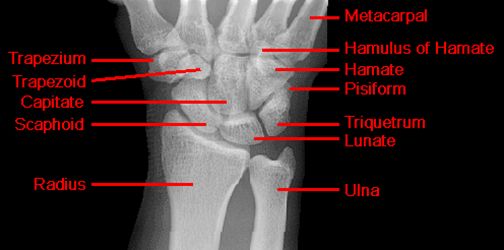

正常腕关节

疼痛科怎么理疗疼痛科医生、康复理疗科医生、针刀针灸医生应掌握的常见骨科疾病X光片_https://www.jmylbn.com_新闻资讯_第23张